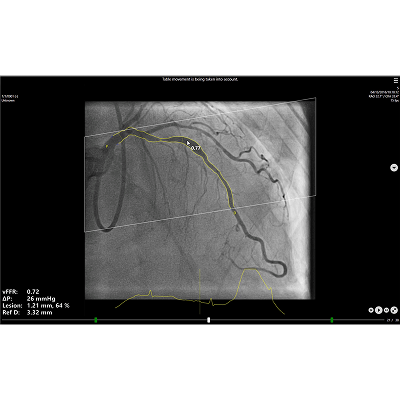

The vFFR workflow builds a 3D reconstruction of coronary artery and assesses pressuredrop, resulting in a vFFR value. Furthermore, with the 3D reconstruction anatomicalesion information is provided, like the percentage stenosis.

Functional lesion information

Pressure drops in coronary artery

vFFR value

Anatomical lesion information

Lesion diameter

Percentage stenosis

Reference diameter